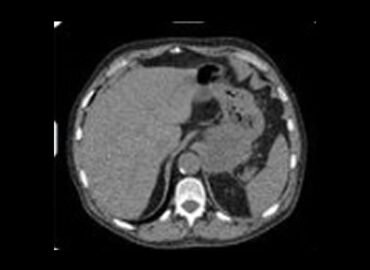

Paciente masculino de 66 años de edad. MC: Dolor abdominal de curso subagudo, intenso, en epigastrio. EX. Físico: Abdomen […]